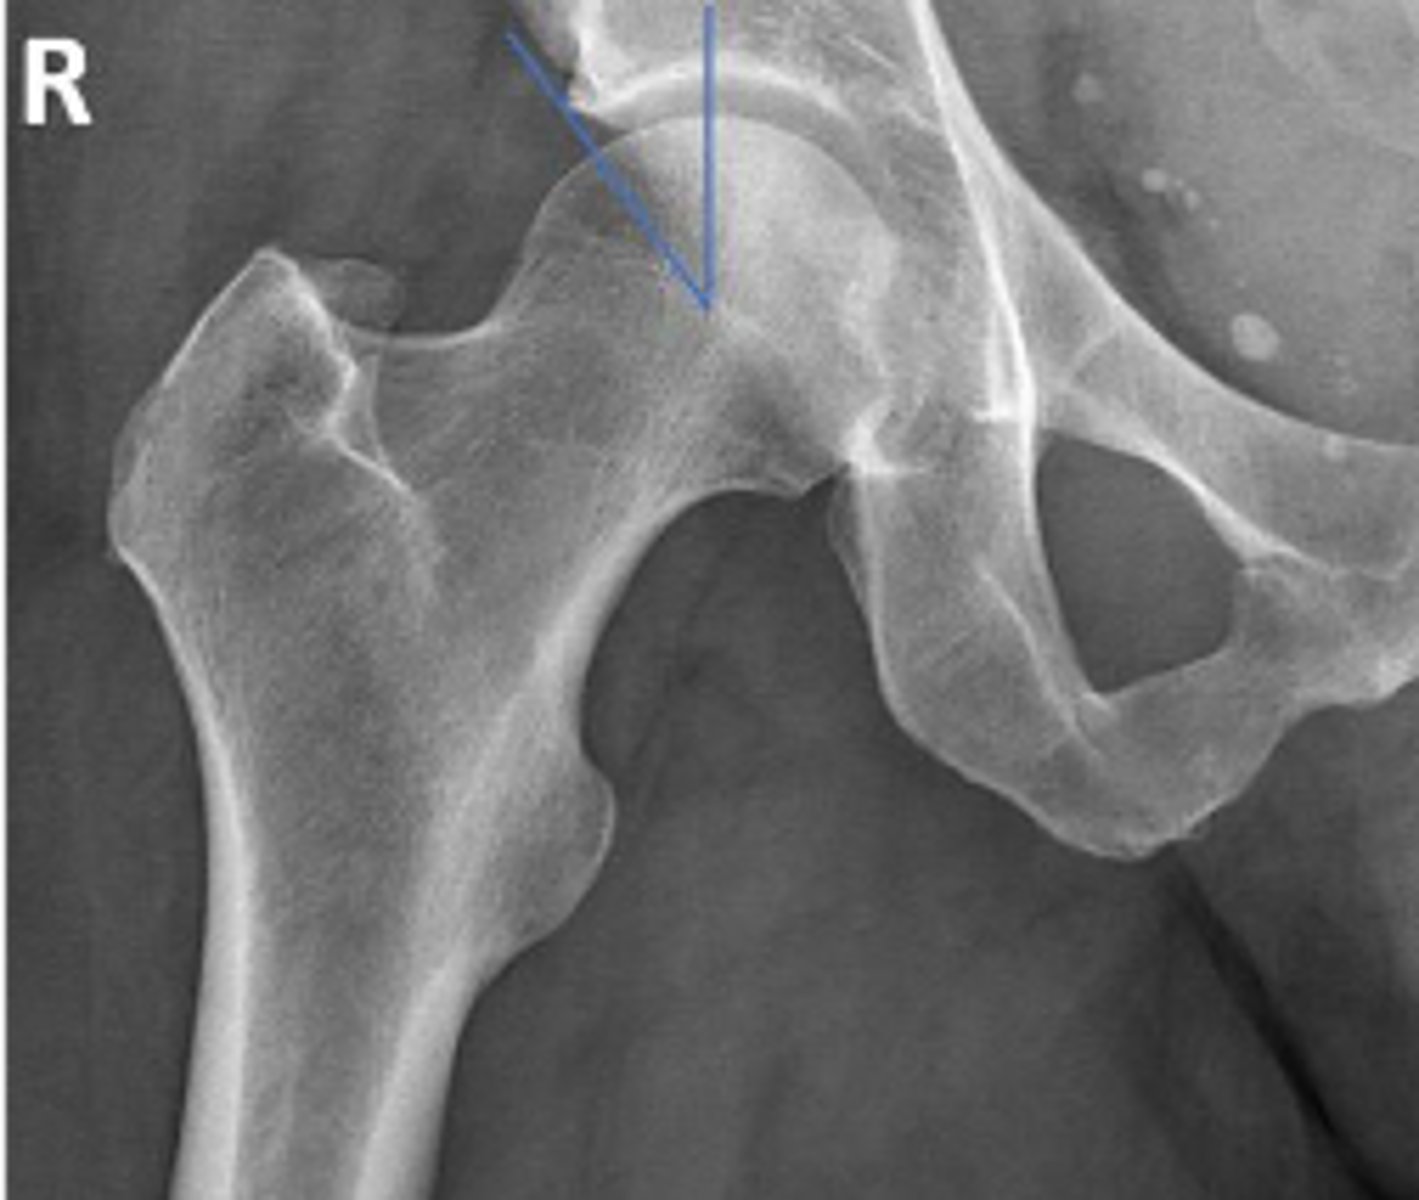

Posterior hip dislocation

What is most significant radiographic finding?

Femoral angle

What is the name of the assessment?

120-130 degrees

What is the normal range for this assessment?